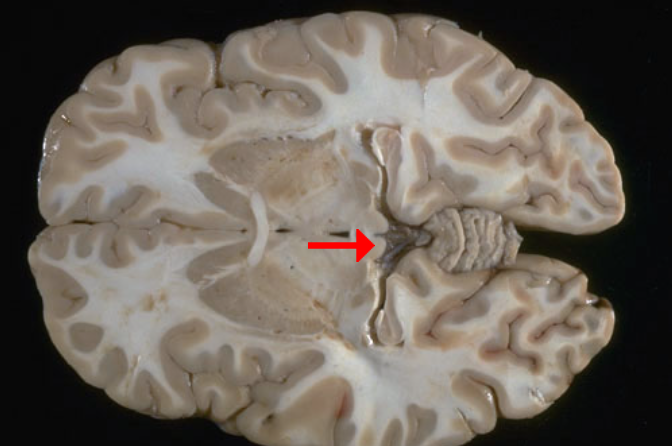

Label this brain structure

Cerebral aqueduct

Label this brain structure

Superior colliculi

Name this brain structure

Fornix

Label this brain structure

Pineal gland

Label this brain structure

Sylvian fissure

Label this brain structure

Superior temporal gyrus